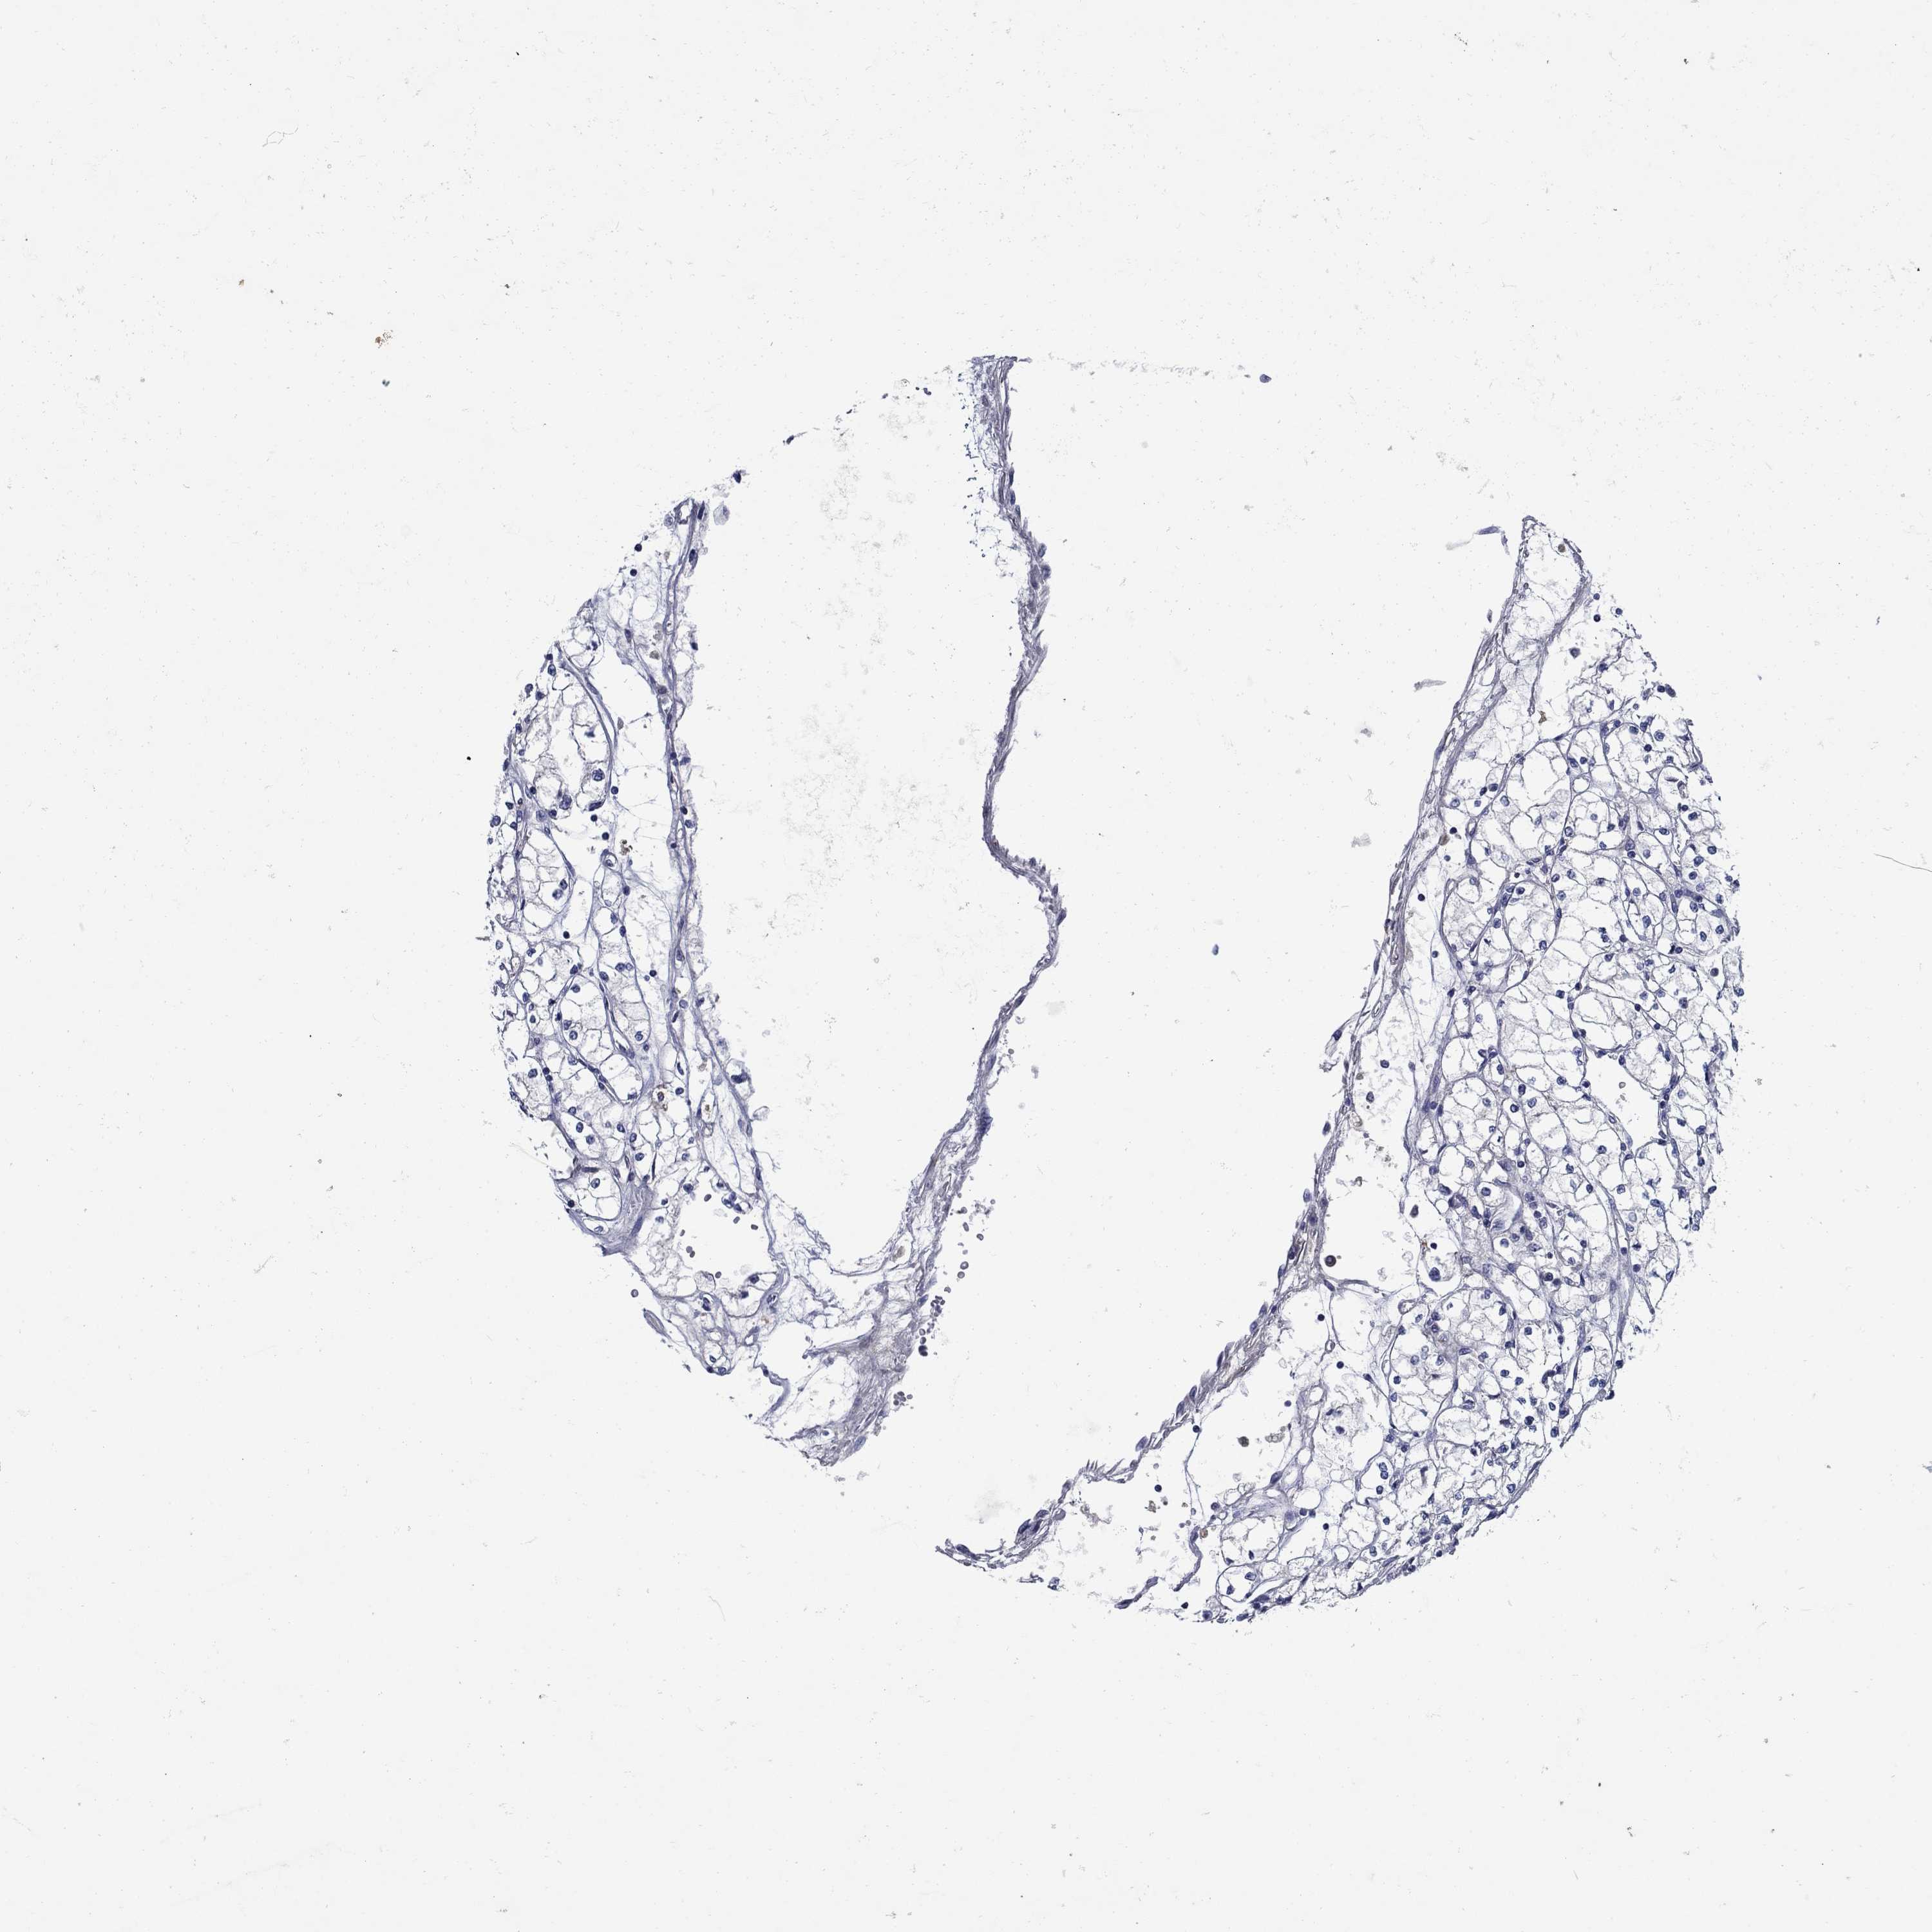

SULT2B1

KICH TCGA KIRC TCGA KIRC VALIDATION KIRP TCGA PROTEIN RCC CPTAC PROTEIN EXPRESSION